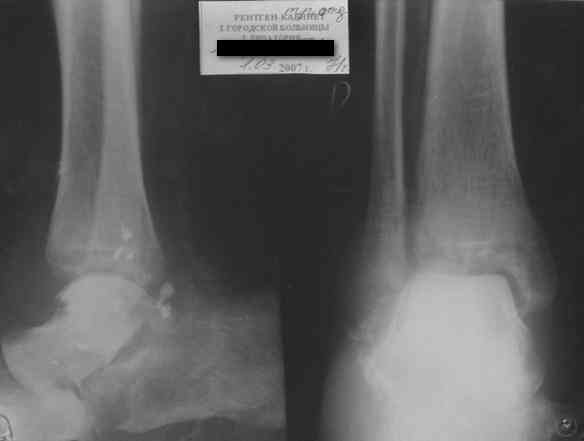

Уважаемый Александр! Как обещал представляю Р-граммы и операционные фото.

Последний снимок

Мнение по поводу тарана? АН есть?

Типичная картина некроза.

На мой взгляд, у больного асептический некроз таранной кости, осложненный гнойным артритом голеностопного сустава (по снимку не понятно, что это - фистулография или простая рентгенограмма). Оптимален артродез голеностопного сустава, объем резекции таранной кости определится только интраоперационно. Большая проблема - метод фиксации. Работая, в основном, с пациентами пожилого и старческого возраста могу сказать, что ЧКОС они переносят плохо. Адекватный уход за аппаратом возможен только в условиях стационара. Возможность самостоятельной работы с аппаратом, например для ликвидации укорочения, крайне сомнительна. Кроме того, укорочение 3 см (до 5 см) у данной категории больных легче компенсировать ортопедической обувью. К сожалению и фиксирующие повязки (гипсовые и различные "касты")- не лучший вариант для пожилых людей (пролежни и флектены просто на "ровном месте"). В данном случае я бы применил простую "фиксирующею" компоновку аппарата Илизарова, с возможностью "отступления" к голеностопному брэйсу (тутору). Основная задача - максимальное восстановление самообслуживания больного и, по возможности, избежать "этапных" операций.